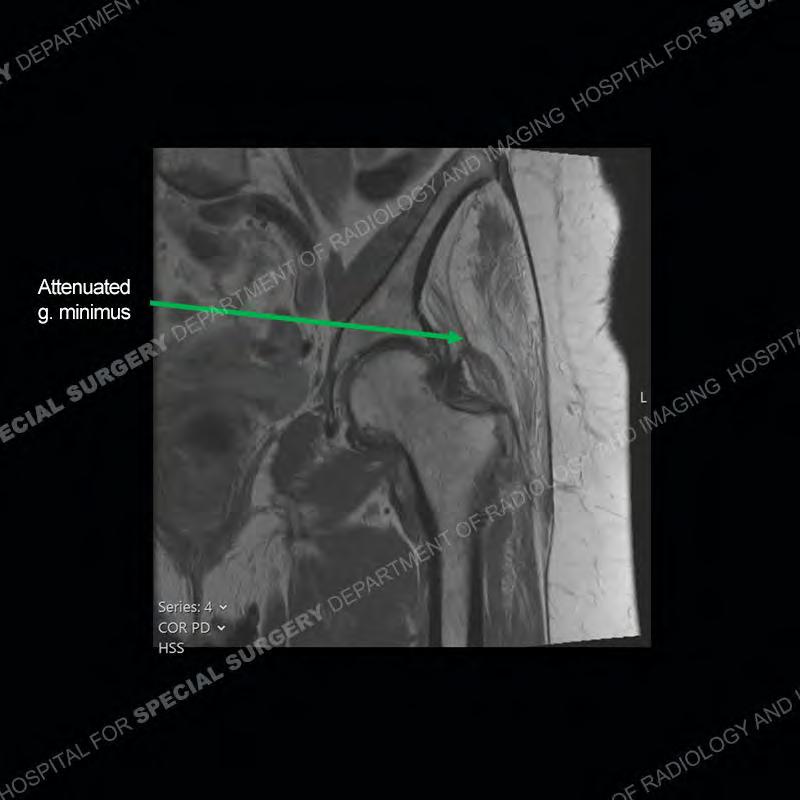

The radiograph is not particularly contributory in this case. The MRI demonstrates markedly abnormal architecture of the gluteus minimus and anterolateral band of the gluteus medius. Portions of the tendons are high signal, portions are highly attenuated, and portions are disrupted. A large, complex fluid collection is present in the adjacent soft tissue.

Not as much of a diagnostic dilemma as many of the other cases shown but just a nice example of the pathology seen of the gluteal tendons and a cause of trochanteric pain. Although, frequently thought of in isolation, trochanteric bursitis or bursal thickening is much more commonly a reactive change to underlying pathology of the subjacent gluteal tendons. The gluteus medius is divided into a posterior band and an anterolateral band. Tendinosis and partial tearing very commonly will involve the gluteus minimus and especially the more posterior fibers and then propagate into the anterior lateral band of the gluteus medius. Involvement of the posterior band of the medius is much less common and engenders a marked degree of functional impairment.

The bursae about the greater trochanter can be a little bit confusing especially given the terminology. Trochanteric bursitis is implied to mean the subgluteus maximus bursa which is present deep to the maximus and just lateral/superficial to the trochanter. That is the bursa involved in this case. In this case the complexity of the bursa relates to the tendon tearing with inflammatory change and probably hemorrhage accounting for the complexity. Two other, less frequently involved bursa are also present. The subgluteus medius and subgluteus minimus bursa are found just deep to the named tendons. Although pathology does frequently follow the previously described pattern it is possible to have isolated pathology to either the medius or minimus.